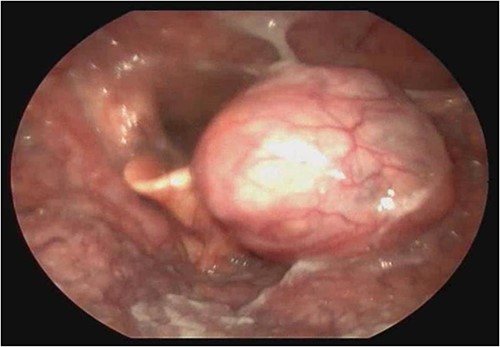

A female patient, 72 years old, sought care reporting intermittent dysphonia for 5 months. She claimed to have hypothyroidism and hypertension, using continuous medication. She denied other symptoms such as weight loss, dyspnea, dysphagia and fever. Two external laryngoscopies had been performed, and a vegetating lesion was found on the left lateral wall of the oropharynx, measuring 3.5 × 2.5 cm with mass effect merging with the left palatine tonsil (Fig. 1). Nuclear magnetic resonance revealed a mixed lesion, containing a cyst with a thick content measuring 23 × 22 × 24 mm (Fig. 2). Given this finding, the chosen procedure was resection by suspension laryngoscopy with the use of CO2 laser. Mass resection of the left tonsil was performed successfully and uneventfully, removing a solid, fibroelastic, 3 × 2 cm mass. Laryngoscopy after 1 month showed good healing, with no evidence of remaining lesions. After histopathological analysis, the tumor was benign and well-delimited (Fig. 3). The main diagnostic hypothesis was myoepithelioma of the oropharynx; however, after analysis of the immunohistochemical evaluation of the specimen, the result was inconclusive between myoepithelioma or PA, favoring the second.

Laryngoscopy showing a vegetating lesion on the lateral wall of the oropharynx.